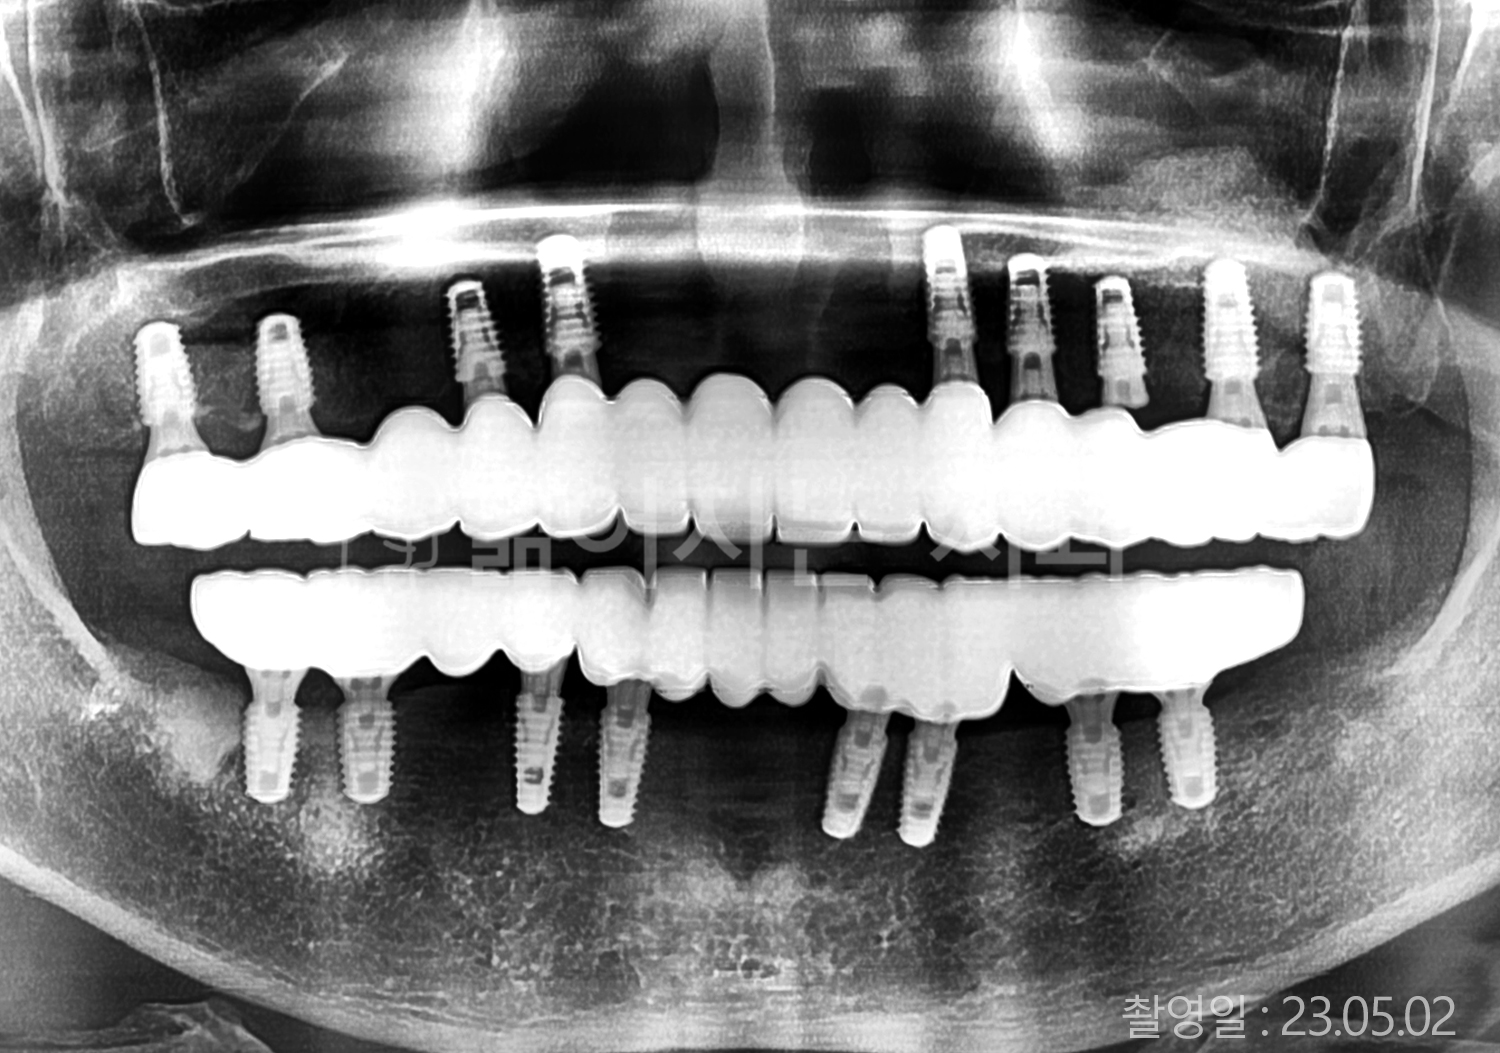

• 60대 고혈압, 고지혈증 전체치아 10개 이상 임플란트

• 70대 전체치아 10개 이상 임플란트

• 60대 전체치아 10개 이상 임플란트

• 50대 전체치아 10개 이상 임플란트

• 50대 고혈압, 고지혈증 전체치아 10개 이상 임플란트

• 60대 고혈압, 당뇨, 고지혈증 전체치아 10개 이상 임플란트

• 80대 고혈압, 당뇨, 골다공증 전체치아 10개 이상 임플란트

• 60대 고혈압 전체치아 10개 이상 임플란트

• 60대 고지혈증 전체치아 10개 이상 임플란트

• 60대 당뇨 전체치아 10개 이상 임플란트